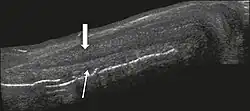

Penile trauma can result from a blunt or penetrating injury, the latter being rarely investigated by imaging methods, almost always requiring immediate surgical exploration. In the erect penis, trauma results from stretching and narrowing of the tunica albuginea, which can undergo segmental rupture of one or both of the corpora cavernosa, constituting a penile fracture.[1]

![Figure 4 A: Ultrasound of the penis, right lateral view. Longitudinal section showing rupture of the tunica albuginea with an adjacent 1.92 cm hematoma (between calipers), due to trauma.[1]](./_assets_/Ultrasonography_of_ruptured_tunica_albuginea.jpg) Figure 4 A: Ultrasound of the penis, right lateral view. Longitudinal section showing rupture of the tunica albuginea with an adjacent 1.92 cm hematoma (between calipers), due to trauma.[1]

Figure 4 A: Ultrasound of the penis, right lateral view. Longitudinal section showing rupture of the tunica albuginea with an adjacent 1.92 cm hematoma (between calipers), due to trauma.[1]